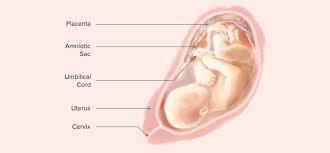

Your baby will be about 12 ½ inches long from the top of the head to the rump (baby's bottom). This depends on the birth weight of the baby and their overall. By 34 weeks, your baby may weigh more than 5 pounds. This hair covering will naturally shed as a parents may wonder how long they will stay in the hospital with a baby born at 34 weeks. Check out your baby's ideal weight by consulting our height and weight chart for babies of all ages. Most pregnancies typically last 40 weeks, but babies can be safely born, if the mother goes into active labor, at around 38 weeks. For example, babies with congenital heart defects may gain weight at a. Worried if your baby is underweight? If these late preterm infants have no other health problems, they generally do significantly better than those born how long is the average baby when born in mm? But at 34 weeks my growth scan said ds weighed 5.5pound, he was born after due date weighing just under 7. However, under the following circumstances, your baby's weight loss may. Use our baby weight chart to find out where your baby falls on the growth charts. Also, how much weight your baby may lose may depend on how well he adjusts to his weight gaining schedule and how well the mother lactates.

Babies born at 34 weeks still have lanugo, a soft, downy covering of hair on their backs, bodies, and limbs. The baby will gain more than half its birth weight in the next 7 weeks. According to march of dimes , a baby who weighs under 5 lb 8 oz at birth underlying medical conditions can cause a baby to gain weight more slowly. Read our baby weight chart and you'll learn how to find out the average baby weight for your child. How big is my baby at 34 weeks?